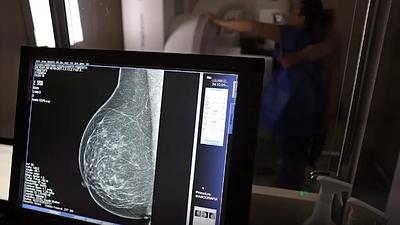

mamacancer.png

Governo incorpora cinco procedimentos contra câncer de mama no SUS

09/12/2024, 12:40

De acordo com a pasta e em razão da importância do diagnóstico precoce, a linha de cuidado do paciente com câncer de mama passa a ser totalmente integrada dentro do Programa Mais Acesso a Especialistas.

Mais mulheres chegam ao SUS no Rio para o exame de mamografia

07/03/2025, 14:40

A rede municipal do Rio tem oferta plena de mamografia e, em 2024, 153 mil cariocas realizaram o exame, que é essencial para o rastreio e diagnóstico da doença.